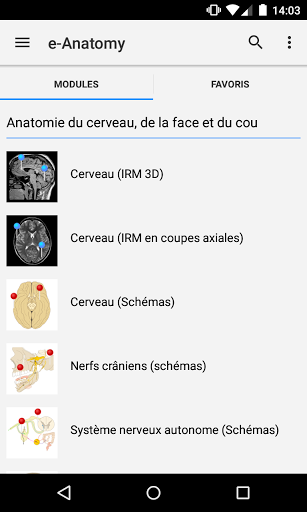

IMAIOS e-Anatomy es un atlas de anatomía humana para médicos, radiólogos, estudiantes de medicina y técnicos en radiología. Echa un vistazo a más de 26 000 imágenes médicas y anatómicas de forma gratuita antes de suscribirte a nuestro detallado atlas de anatomía humana.

e-Anatomy se basa en el galardonado atlas en línea IMAIOS e-Anatomy. Lleva contigo la referencia más completa de anatomía humana, dondequiera que vayas, en tu dispositivo móvil o tableta.

e-Anatomy tiene más de 26 000 imágenes que contienen series de imágenes en vistas axiales, coronales y sagitales, así como radiografías, angiografías, imágenes de disección, gráficos anatómicos e ilustraciones. Todas las imágenes médicas fueron etiquetadas cuidadosamente, más de 967 000 etiquetas disponibles en 12 idiomas, incluida la Terminologia Anatomica latina.